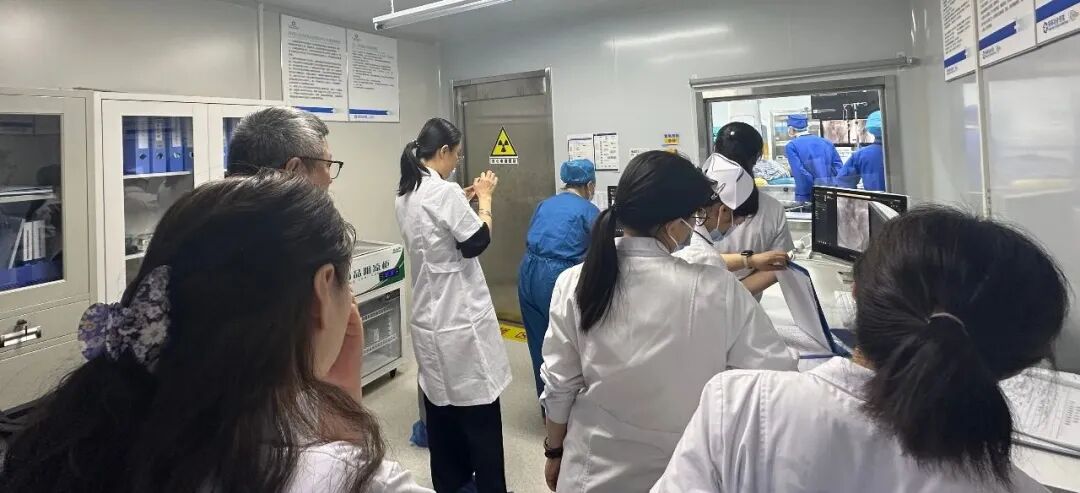

活动伊始,于黎明教授在DSA设备的精准辅助下,为现场同仁进行了DSA下下肢静脉顺行造影手术实操演示。

在学术讲座环节,于黎明教授分享《介入诊疗技术的临床应用与进展》,于教授系统梳理神经介入、心脏介入、外周血管介入、综合介入治疗等介入治疗特色。内容覆盖高血压、糖尿病、肿瘤、心血管、外周血管、前列腺增生等多种疾病的介入治疗策略。

讲座结束后,现场进入热烈的交流讨论环节。双方围绕学科建设、技术提升等方面深入探讨,并通过疑难病例研讨,将理论知识与实际病例相结合。于黎明教授结合自身临床经验,针对我院在大血管外科、静脉血栓防治、肿瘤微创介入与急危出血救治等介入治疗方面现状,提出了诸多建设性意见,为我院介入治疗技术的提升和学科发展供了有力支持。